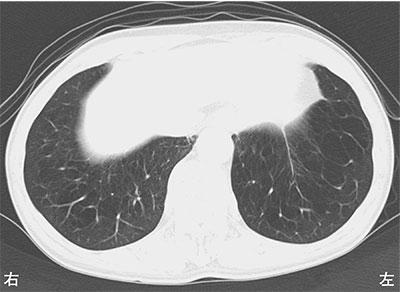

80歳の男性。胸部CTを示す。この患者で予想されるのはどれか。

1

肥満

2

残気量の低下

3

一秒率の低下

4

気道抵抗の低下

5

肺コンプライアンスの低下